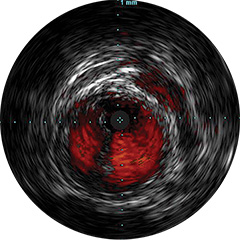

Figura 2